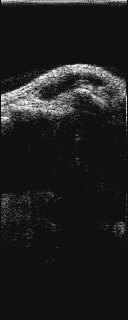

エコ−画像

長 軸           短 軸

腫瘤があるのがはっきりとわかる。

中身は、ゼリ−様の液体である。

(長軸像では、左が中枢、右が末梢)